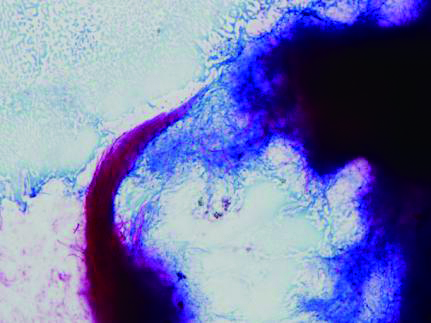

| 图 3 胸水标本表现出分歧杆菌革兰染色阳性提示奴卡菌感染(1 000×) |

| 图 4 抗酸染色见不典型分歧杆菌 |